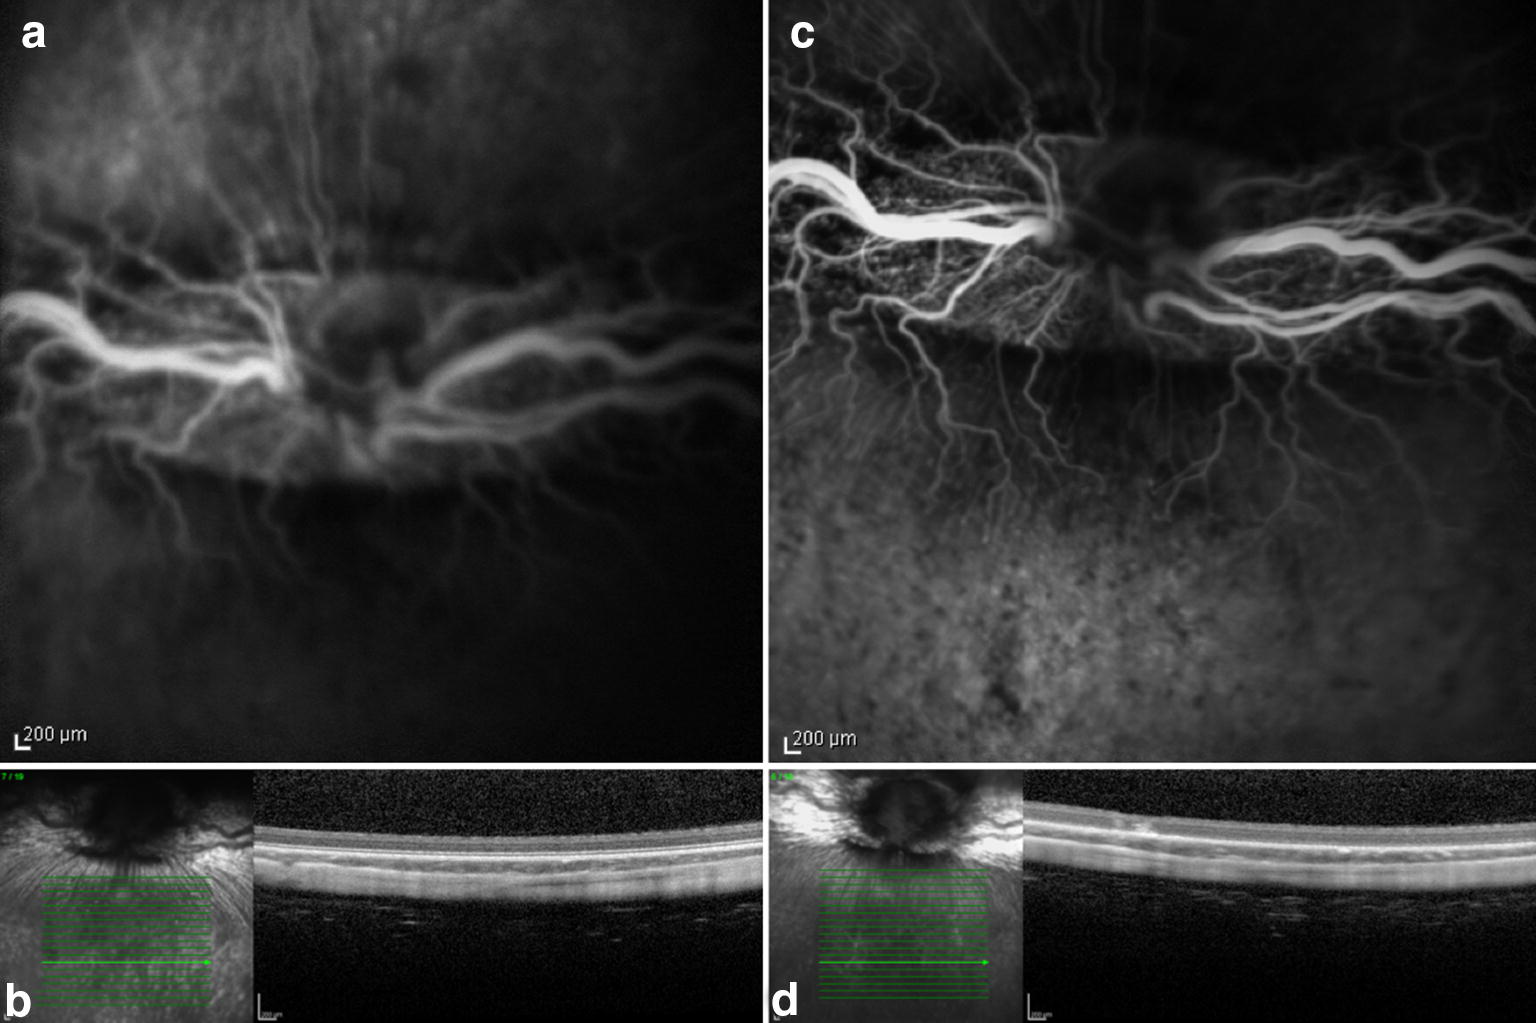

Fig. 4.

Preoperative (a and b) and seven days postoperative (c and d) fluorescein angiography and OCT. Rabbit (no. 6) exposed to 435 nm illumination after systemic administration of lutein. Postoperative hyperfluorescence (c) corresponds to the exposed area and increased reflective of the inner and outer layers of the retina seen on OCT (d)

Fig. 5.

Preoperative (a and b) and seven days postoperative (c and d) fluorescein angiography and OCT. Rabbit (no. 8) exposed to 435 nm illumination after systemic administration of lutein. Postoperative hyperfluorescence (c) corresponds to the exposed area and increased reflective of the inner and outer layers of the retina seen on OCT (d)